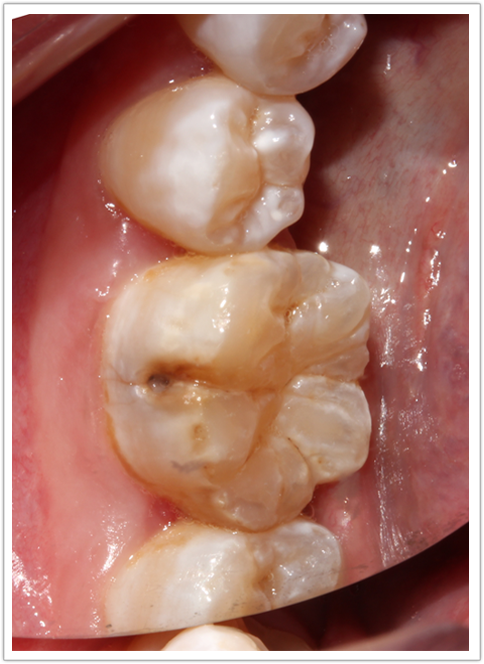

现病史:几日前发现右下后牙发黑,影响美观,特来诊。

检查:颌面部未见异常,口内查:46颊面沟龋坏达牙本质层,温度测试正常。

诊断:46中龋

治疗过程:46.去腐备洞 ,隔湿干燥,光照玻璃离子垫底,纳米充填, 调合,抛光。